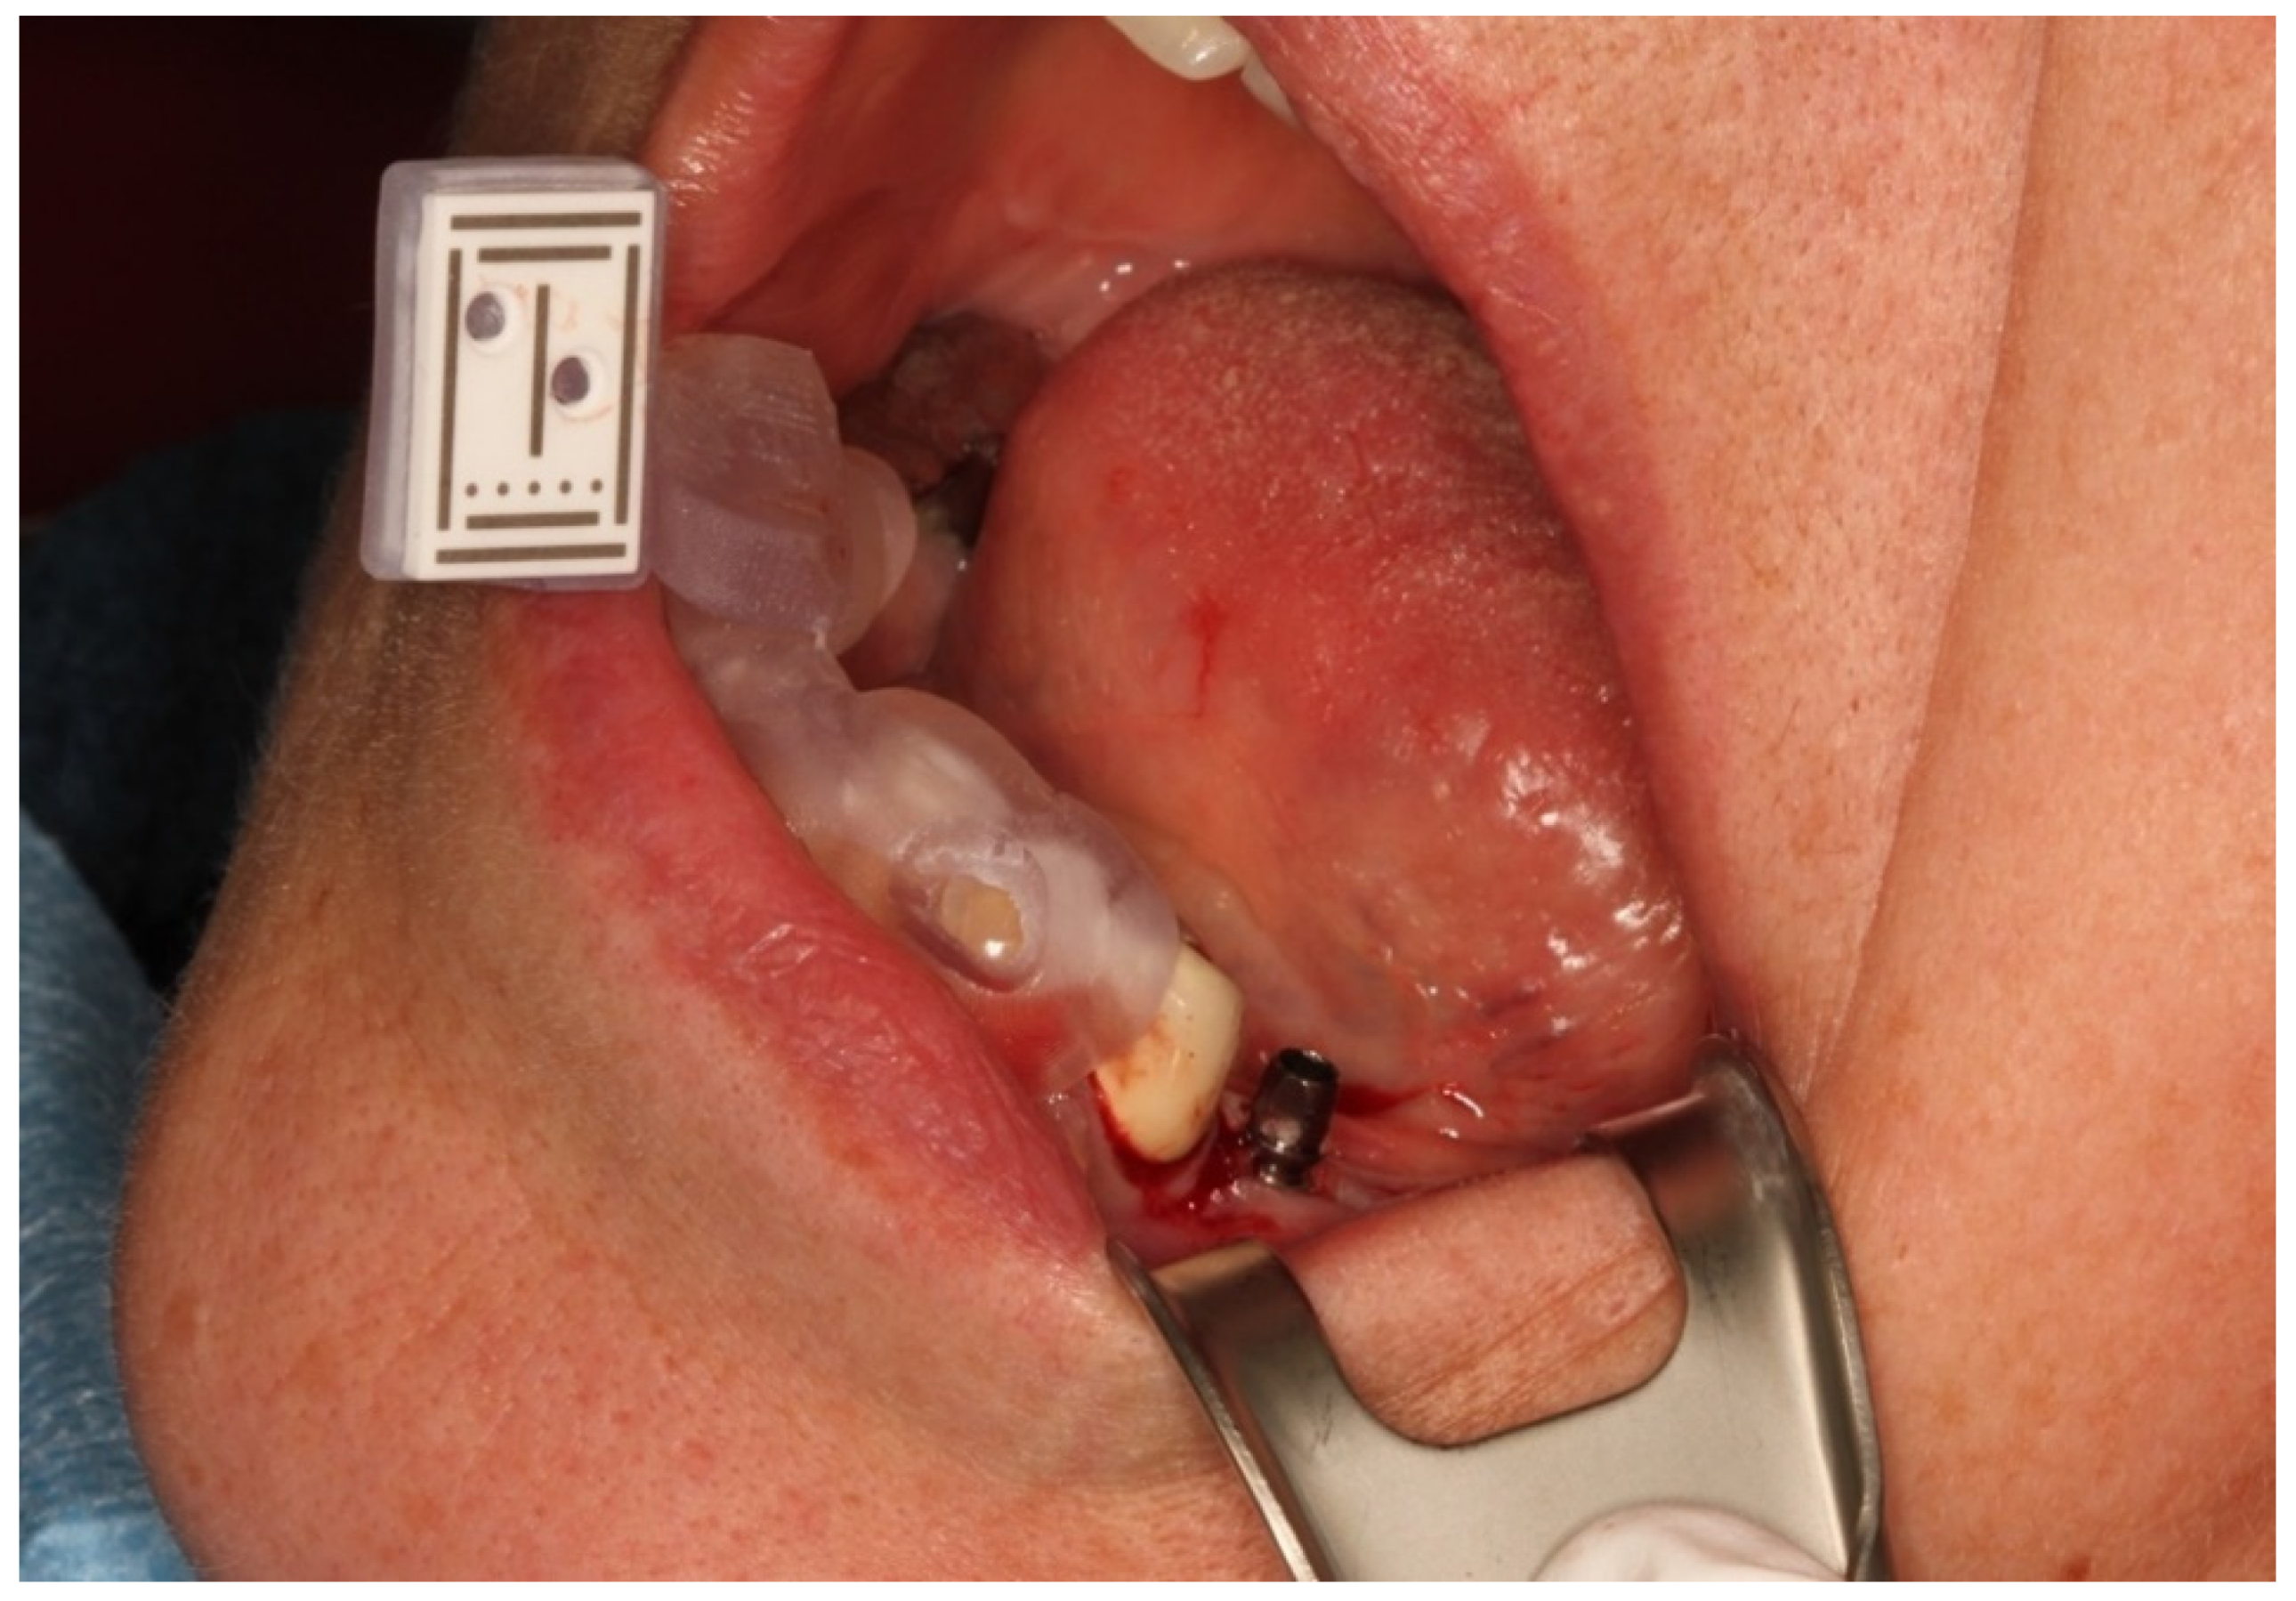

2.3. Reference Marker

2.4. Registration of the Implant Position